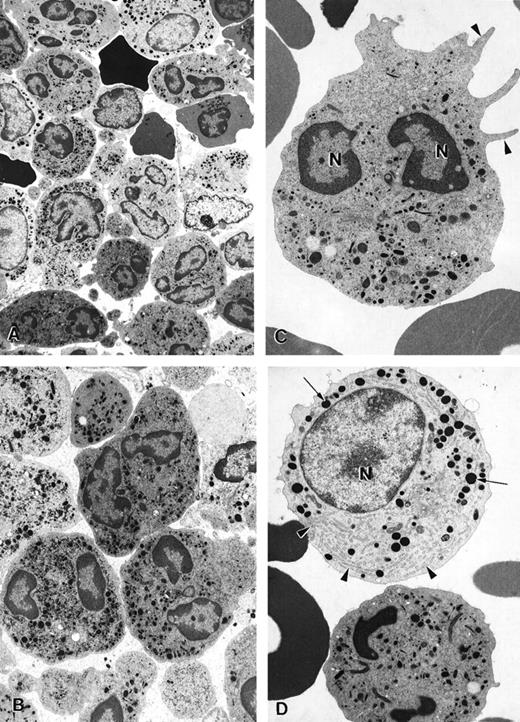

The ultrastructure of bone marrow cells from patient 2 and a healthy volunteer donor was investigated before and during G-CSF therapy using electron microscopy (Figure 4). The bone marrow aspirate from a healthy volunteer contained predominantly neutrophils at various stages of maturation and immature red blood cells (Figure 4A; arrowheads). Few degenerating cells and minimal cellular debris were observed. In contrast, numerous degenerating cells (indicated by arrows) were present in the bone marrow aspirate from a patient with myelokathexis. In the degenerating cells, typical features of apoptosis were present, including the convoluted nucleus in an otherwise still intact cell. The granules (G) were aggregated, and the heterochromatin was concentrated in distinct, dense granular patches located on the inner surface of the nuclear membrane (Figure 4B). At higher magnification, apoptotic features such as cytoplasmic blebbing (arrowheads) and intense condensation of chromatin in the nucleus (N) were readily apparent in neutrophils (Figure 4). Macrophages were observed with numerous phagosomes that contained cellular debris as a result of phagocytizing senescent cells (Figure 4D). These apoptotic features were not present in the bone marrow aspirate from a healthy volunteer. These data indicated that accelerated apoptosis occurs in vivo in the myeloid precursor population in patients with myelokathexis.

Electron micrographs of bone marrow from patient 2 before granulocyte colony-stimulating factor treatment.

(A) Low magnification of the bone marrow shows degenerating cells (*), few mature neutrophils (**), and promyelocytes (arrows). Neutrophils with convoluted nuclei (arrowheads), a sign of early apoptosis, are observed. Magnification ×4000. (B) Macrophage in the bone marrow contains several phagosomes (arrows) with cellular debris of neutrophils. Neutrophil (arrowheads) with a distinguishable nucleus (*) and granules is discernible in 1 of the phagosomes. N, macrophage nucleus. Magnification ×6500. (C) Neutrophil in an early stage of apoptosis. The nucleus is convoluted (arrowheads), and the chromatin is condensed and distinctly circumscribed, forming dense granular masses (*) along the inner surface of the nuclear envelope. Magnification ×7500. (D) Neutrophil in a later stage of apoptosis. The cell shows cytoplasmic blebbing (arrowheads) and cellular fragmentation (arrow). N, nucleus. Magnification ×13,000. (E) Promyelocytes observed in the bone marrow. The cell at the bottom left appears normal and has a large, round nucleus (N), numerous granules, and a well-developed rough endoplasmic reticulum (arrows). The cell at the top right is apoptotic, as indicated by the fragmented nucleus (*), and has distinct areas of condensed chromatin (arrowheads). Magnification ×5500.

To investigate the cellular and molecular defects responsible for ineffective granulocytopenia in myelokathexis, we studied 4 patients from 2 unrelated families. The morphologic appearance of bone marrow-derived cells from these patients, as determined by light and electron microscopy, demonstrated that mature marrow and blood neutrophils, as well as myeloid-committed precursors, underwent degenerative changes that were characterized by profound apoptotic features, including extended cytoplasmic membrane blebbing, granule aggregation, cytoplasmic vacuolization, and intensive condensation of heterochromatin in the nucleus (Figure 4). Such apoptotic cells became hypofunctional and were removed from the intramedullary space by bone marrow macrophages through phagocytosis (Figure 4).